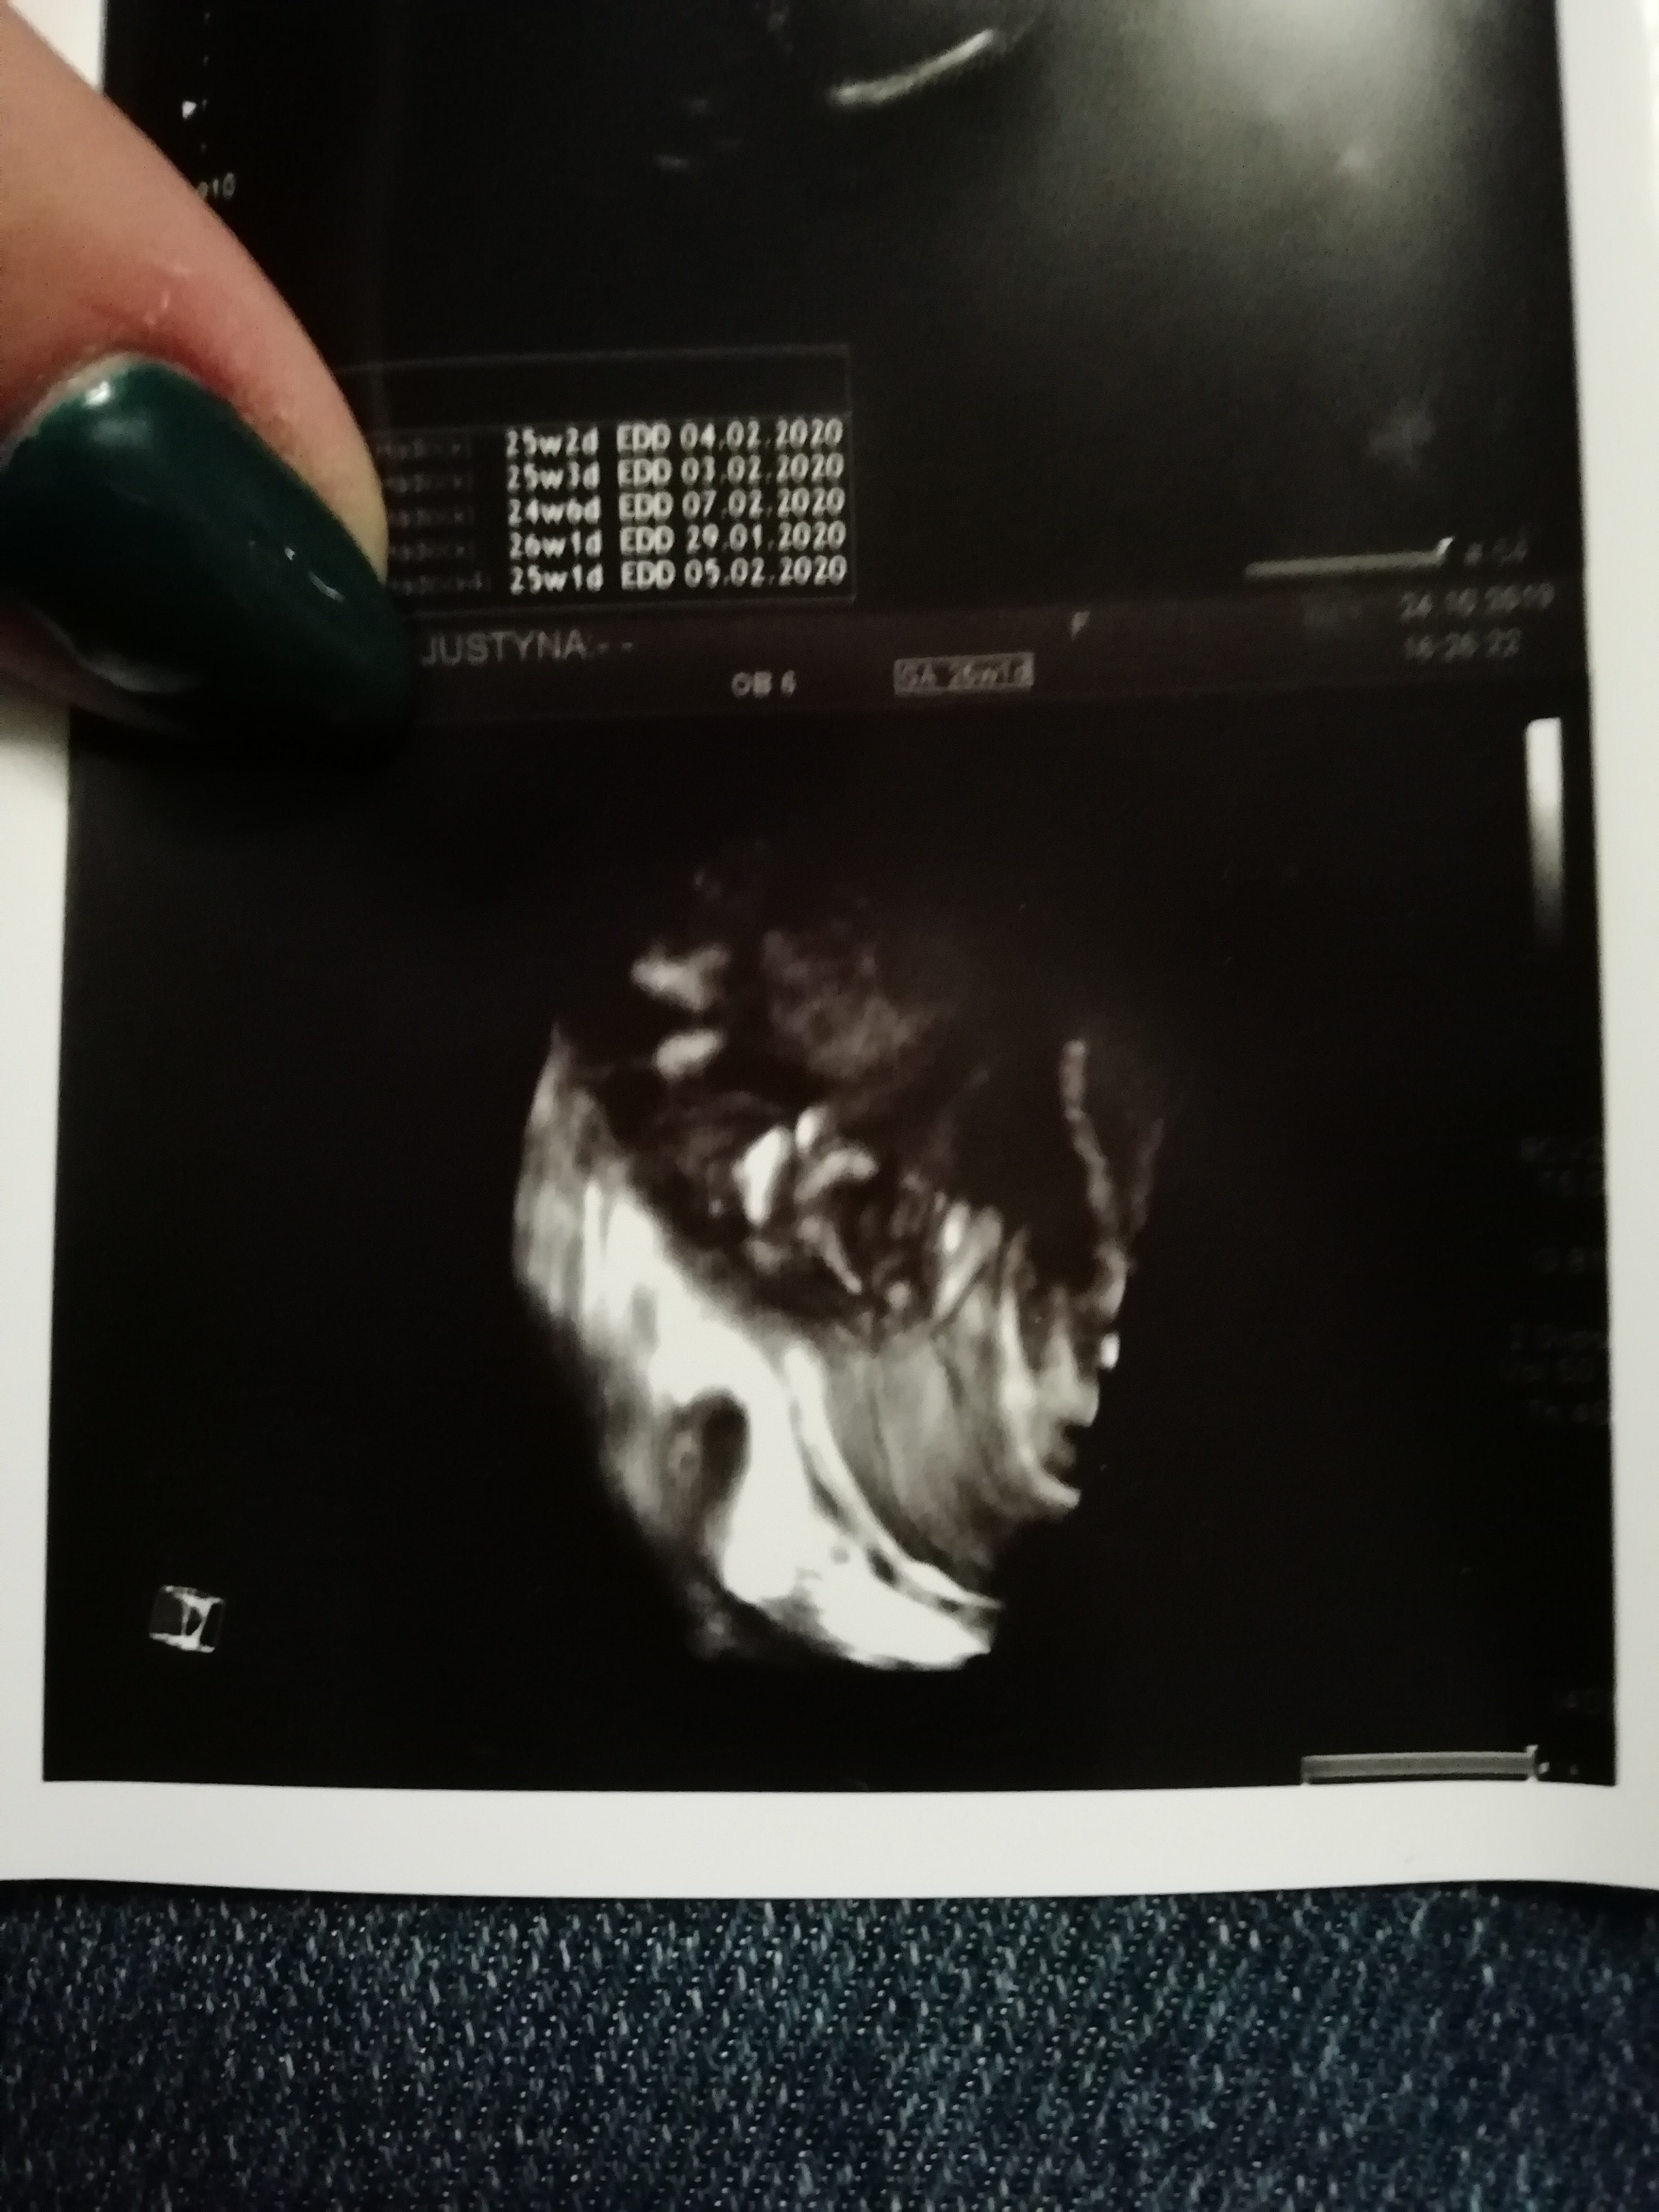

Przedatawiam wam dziewczyny Błażeja :)

A tu jeszczw nochalek raz :)

IMG_20191024_205527.jpg